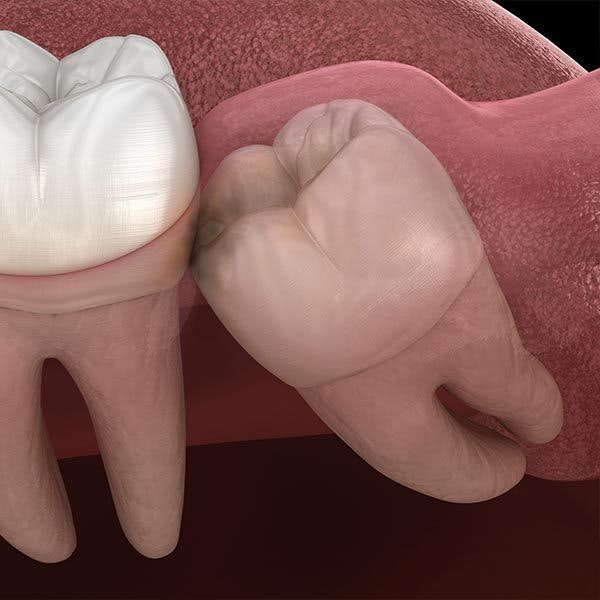

View on GoogleWisdom Teeth Extraction Can Prevent Further Damage

misalignment. Removing them promptly is crucial to preventing further issues

like periodontal disease and cavities.

Patients frequently wonder: If a general dentist can perform my surgery, like wisdom tooth removal, why do I need an oral surgeon? The short answer is that an oral surgeon is versed in a wider array of oral surgery procedures, and is more qualified to handle especially complex cases. When it comes to certain needs, it pays to trust your care to a specialist.